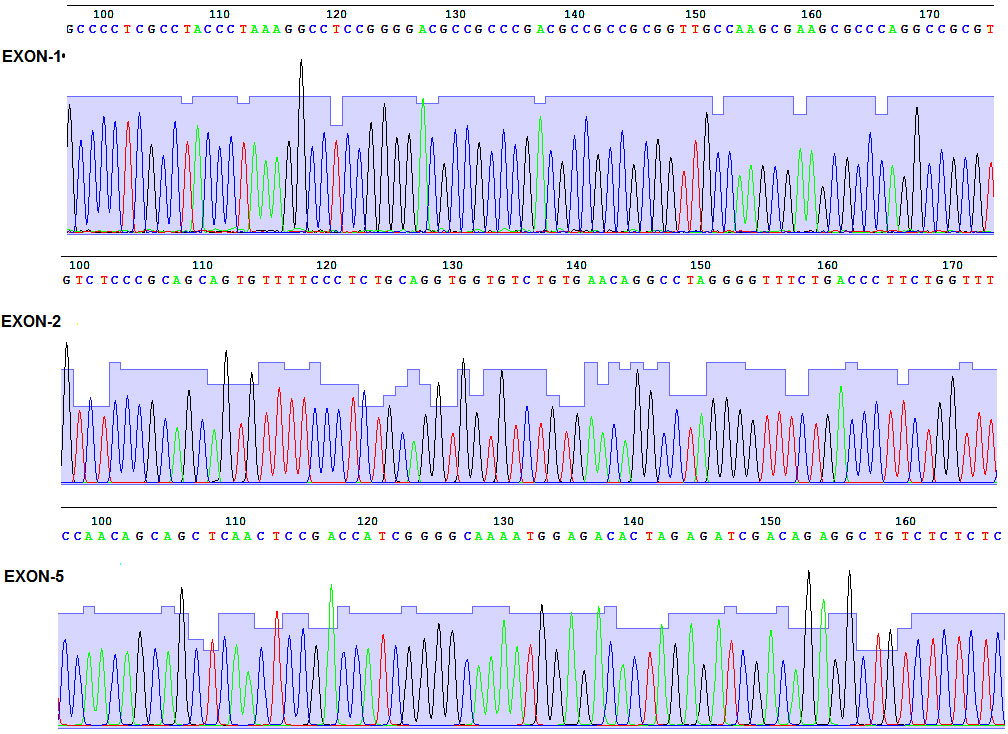

Mutation de TUBB8 et arrêt méiotique de loocyte humain

Pr Stéphane Viville HUS - Strasbourg

Mise en évidence pour la première fois dans l’espèce humaine de mutations d’un gène responsables d’un blocage de la méiose ovocytaire. La fécondation humaine ne peut aboutir que si un ovocyte bloqué en métaphase II fusionne avec un spermatozoïde. Dans l’espèce humaine, la méiose ovocytaire débute en période prénatale et s’arrête...